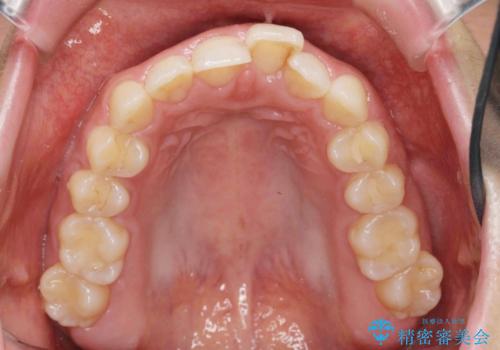

出っ歯に見える前歯の改善 部分ワイヤーとマウスピース矯正

- 出っ歯に見える前歯の改善を希望され、来院されました。

マウスピースでは改善の難しい歯の動きを部分ワイヤー矯正で整えたのち、奥歯の噛み合わせや細かい歯の並びをマウスピース矯正インビザラインで整えていきます。

最終的な前歯の並びに大変満足いただくことができました。